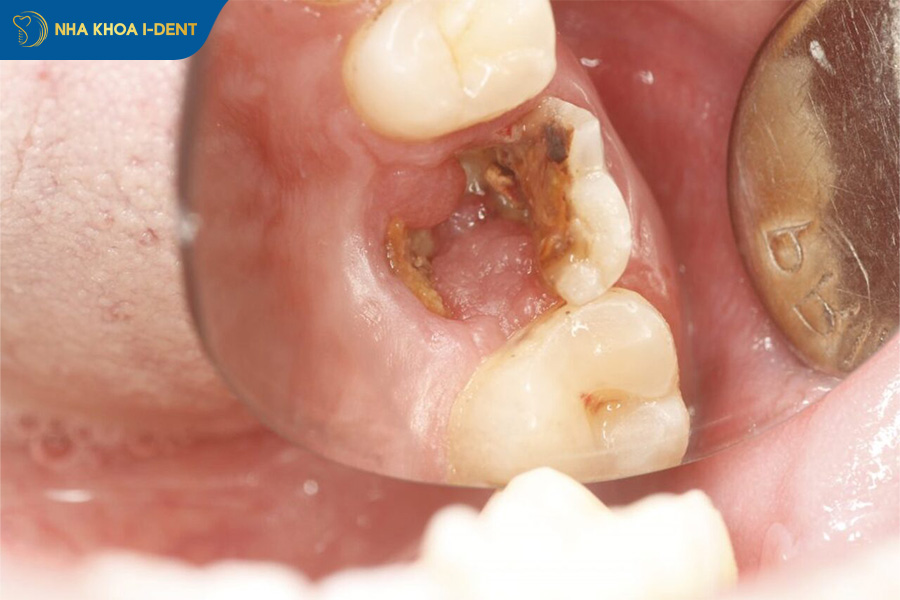

2.5. Răng bị mẻ, vỡ nghiêm trọng

Trong nhiều trường hợp, răng bị mẻ hoặc vỡ nhẹ có thể được phục hồi bằng bọc răng sứ. Tuy nhiên, nếu răng bị vỡ quá nghiêm trọng, đặc biệt là vỡ sát chân răng hoặc mất phần lớn thân răng, việc bọc sứ có thể không còn khả thi. Khi cấu trúc răng thật không đủ để nâng đỡ mão sứ, mão sứ sẽ khó cố định chắc chắn và dễ bị bung hoặc gãy trong quá trình ăn nhai. Lúc này, bác sĩ có thể cân nhắc các giải pháp khác như điều trị tủy, đặt chốt trong ống tủy hoặc thậm chí nhổ răng và phục hình bằng Implant.

Răng bị vỡ hết thân răng